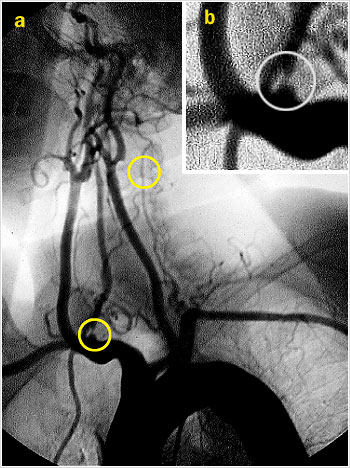

La arteriografia de los troncos supra aórticos y de la circulación intracraneana, permite ver con gran resolución los vasos del territorio posterior desde su origen. A la vez permite ver la circulación anterior o carotídea.

La imagen del arco aórtico y de la porción extra craneana de carótidas y vertebrales (Fig. 3 a), proyección oblicua anterior izquierda, muestra una estenosis crítica de la vertebral derecha en su origen (Fig 3b), asi como también una marcada hipoplasia de la vertebral izquierda. (círculos). En esta proyección también se demuestra una estenosis de ± 50% de la carótida interna en su origen.

Arco aórtico y de la porción extra craneana de carótidas y vertebrales.

En la imagen de la circulación intracraneana (Fig 3 c, visión antero-posterior) se ve claramente la hipoplasia del segmento V4 de la vertebral izquierda.

Circulación intracraneana.